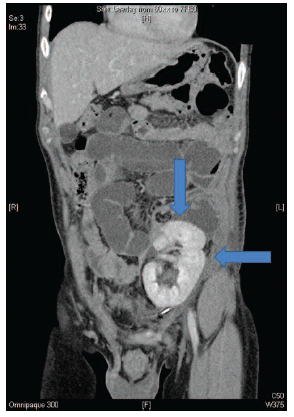

Initially, he was treated with nil by mouth, intravenous fluid, and antimicrobial agents; however, overnight his symptoms worsened with increased pain, abdominal distention, and decreased bowel sounds. An abdominal radiograph showed dilatation of the small bowel, suggestive of an obstruction (Figure 1). An axial computed tomographic scan of the abdomen showed distention of the small bowel with a transition point in the left lower quadrant above the transplanted kidney (Figure 2). The patient underwent an exploratory laparotomy, reduction of the small bowel loop (which was distended but still viable), entrapped through a defect in the peritoneum covering the transplanted kidney (Figure 3). He did not require a bowel resection, and the peritoneal defect was closed with absorbable sutures. His recovery was uneventful.

Figure 2. Computed Tomography Scan of the Abdomen Showed Small Bowel Obstruction With a Transition Point (Vertical Arrow) in the Left Lower Quadrant Above the Transplanted Kidney (Horizontal Arrow)